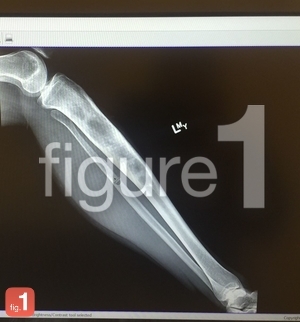

Figure 1

Figure 1, una nueva aplicación conocida como el ‘Instagram para médicos’, promete revolucionar la forma en la que los doctores buscan opiniones médicas sobre casos difíciles y únicos. No obstante, ya ha levantado suspicacias y dudas sobre el tratamiento que recibe en esta red social la privacidad de los pacientes.

Figure 1 permite a los profesionales médicos compartir fotos y comentarios de aquellos casos clínicos menos comunes e interesantes para la comunidad científica. El principal objetivo es el de proporcionar o buscar asesoramiento, opiniones médicas u opciones de tratamiento de las distintas enfermedades o dolencias.

De acuerdo con Figure 1, todas las imágenes publicadas son revisadas previamente con mucha cautela y precisión para eliminar toda la posible información personal que contengan, como es el caso de determinados detalles físicos que podrían identificar a los pacientes (caras, tatuajes, piercings, etc.). Se oscurecen o se eliminan utilizando las propias herramientas de edición que integra la aplicación.